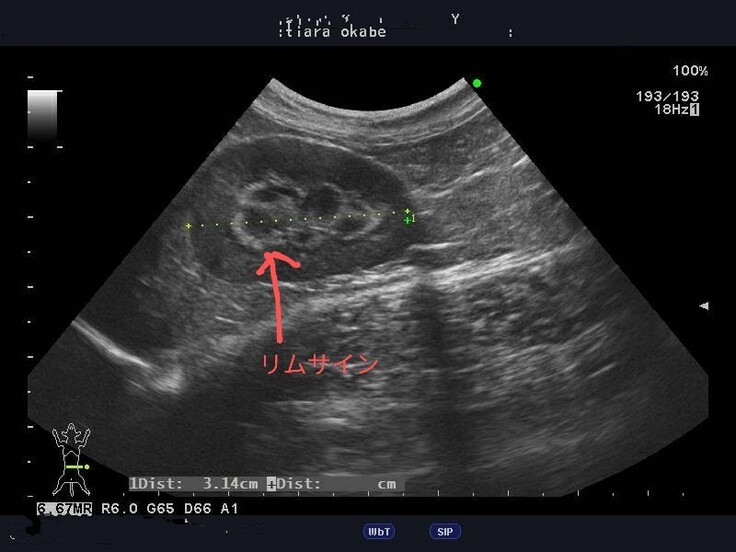

理由は、3か月の間に胃腸炎になり拗らせたことでFIP発症の原因の一つである免疫力が弱いこと、今は治療をする必要もなく問題ではないが心雑音があること、0.8以上が望ましいA/G比が0.9~0.8に戻ってしまったこと、FIPの発症で腎臓にできたリムサインが消えることはなく発症時と変わらないまま残っていること…からです。

【病院から掲載の許諾を得ております】

リムサインは、たんぱく質の塊のような物らしく稀に残ってしまう子もいるようで、これが今後どのように影響してくるのかはデータがなく先生にも分からないそうです。もしFIPでない猫さんにリムサインができた時は腎不全になるとのことなので、これが一番の不安材料になっています。